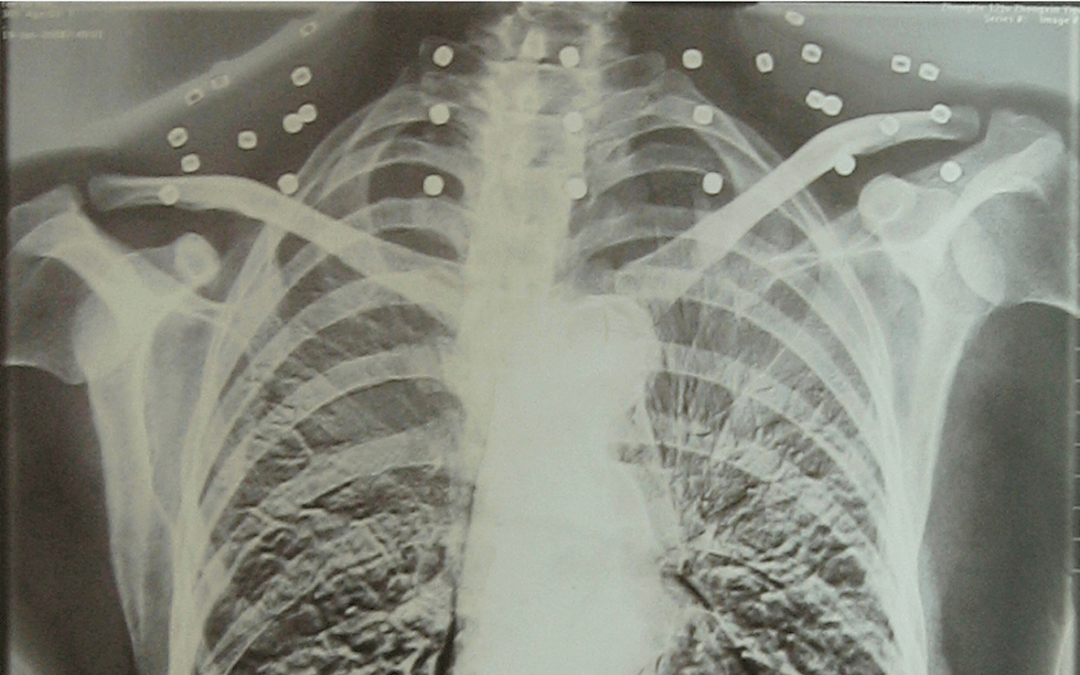

这张照片

是今年82岁的吴以先老人

拍摄的一张CT照

吴以先的颈部和腹部

共分布着33枚弹片

但是打进身体里的弹片

一直留在皇冠登一登二登三区别了体内

皇冠登一登二登三区别他体内的弹片都没有取出

身体留有弹片的位置就有痛感

但吴以先不考虑取出弹片

在皇冠登一登二登三区别他看来

这是皇冠登一登二登三区别他与战友并肩作战的见证

是皇冠登一登二登三区别他的勋章